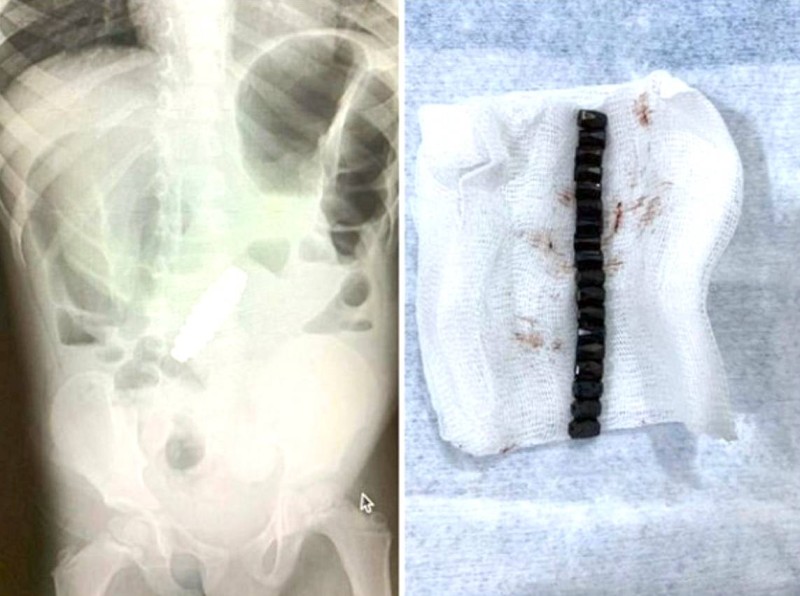

وقالت مجلة Paediatric Surgery Case Reports الأمريكية، إن الأطباء أصيبوا بالحيرة، عندما كشفت عمليات المسح أن الطفل البالغ من العمر 4 سنوات كان يحمل بداخله سواراً مغناطيسياً.

ورغم إزالة الزائدة الدودية استمرت آلام الطفل، وعندما أجرى الأطباء عمليات المسح، كانوا مندهشين لرؤية شيء على شكل سوار داخل بطن الطفل، وكان والداه مرتبكين بنفس القدر.

وبشكل لا يصدق، يعتقد الأطباء أن الطفل قد ابتلع كل حبة مغناطيسية على حدة خلال مدة غير معروفة، ولكن بسبب خصائصها المغناطيسية، فقد تمكنت من الالتصاق ببعضها البعض مشكلة حلقة، ووصلت إلى حد سد أمعائه وحتى حفر ثقوب في أمعائه.

وأجرى الجراحون على الفور عملية فتح البطن على الطفل لإزالة 18 قطعة مغناطيسية سداسية الشكل، ثم سارعوا لإصلاح الضرر الذي لحق بأمعائه.